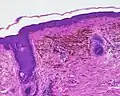

Micrograph of a blue nevus showing the characteristic pigmented melanocytes between bundles of collagen. H&E stain

Micrograph of a blue nevus showing the characteristic pigmented melanocytes between bundles of collagen. H&E stain -

Blue nevus

Blue nevus -